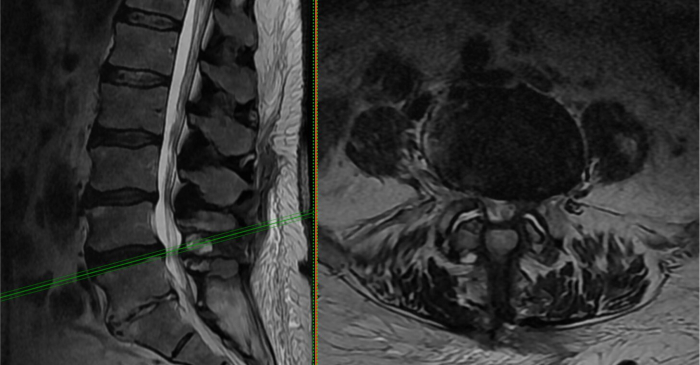

Lumbar Radiculopathy (Sciatica / Pinched Nerve)